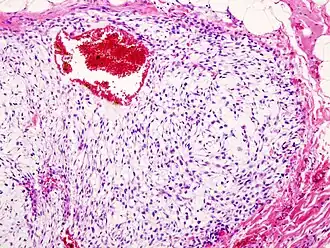

Патологическая анатомия

Хондросаркома — злокачественная опухоль хрящевого строения. Хондросаркома периферической локализации хорошо выявляется в виде плотной опухоли, прилегающей к кортикальному слою кости, иногда прорастающей в кость на различную глубину. В ней могут быть очаги оссификации и петрификаты. Опухоль плотноэластической консистенции, при наличии ослизнения, распада или кровоизлияний — более мягкая, не имеет ясного ограничения от соседней ткани. При разрезе нетрудно определить хрящевой её характер. При микроскопическом исследовании опухоль напоминает иногда хондрому, состоит из незрелых клеток с резко выраженным клеточным атипизмом. Часто рисунок опухоли имеет вид микросаркомы, в которой можно найти участки хрящевой ткани с плохо оформленными ячейками, содержащие неправильной формы хондробласты.